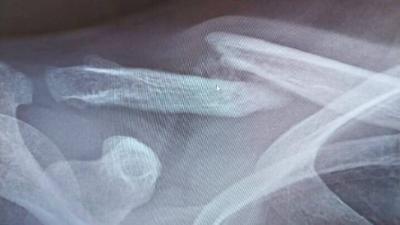

• 27-12-24: Hier hebben we al enkele behandelingen gehad en is er een nieuwe foto gemaakt in het ziekenhuis. Op deze foto was het effect van lasertherapie al direct zichtbaar. Er is een klein wolkje zichtbaar rondom de breuk. Dit wolkje wilt zeggen dat botgenezing bezig is.

Sleutelbeen fractuur 20-10-24 Voor Sleutelbeen fractuur 21-1-25 Na Sleutelbeen fractuur 27-12-24 Tussen